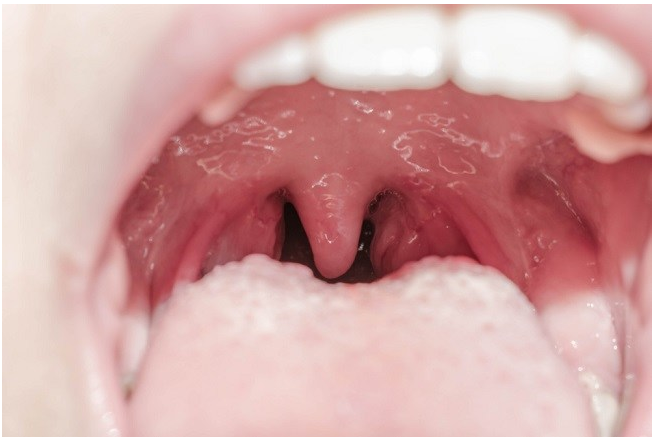

Selain dalam proses pernapasan, laring juga berperan sebagai tempat kotak suara. Ini karena di dalam laring terdapat pita suara yang dapat bergetar, sehingga dapat menimbulkan bunyi. Keberadaan pita suara inilah yang memungkinkan kita berbicara, bernyanyi, dan berteriak.

Di pangkal laring terdapat organ bernama epiglotis. Fungsinya sebagai katup yang akan menutup pintu masuk laring ketika proses menelan makanan maupun minuman. Oleh karena itu, hindari makan sambil berbicara agar epiglotis menutup dengan sempurna dan mencegah tersedak.